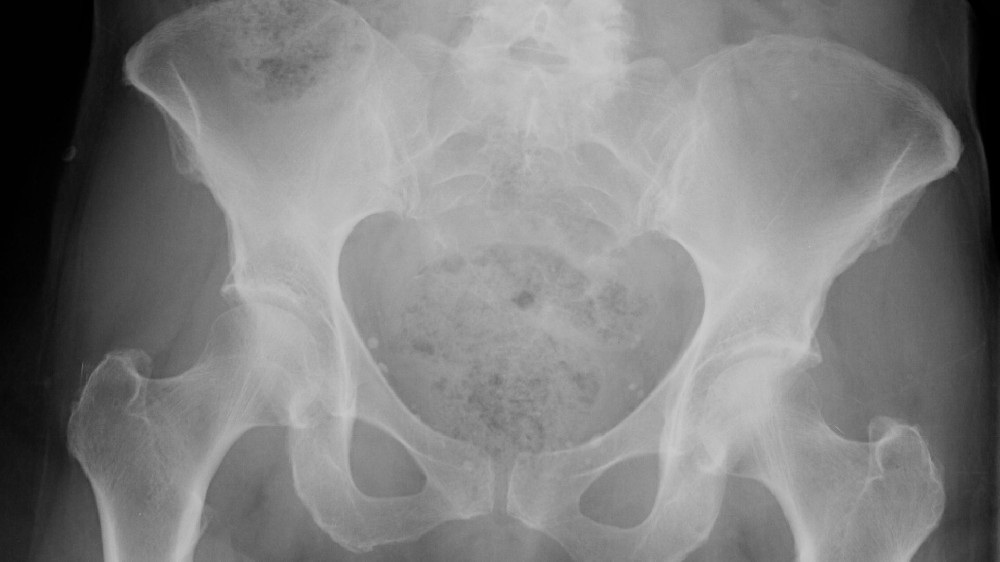

這種罕見的腫瘤主要沿軸向骨骼表現,常影響骶尾部 (約 50%)、顱底 (約 35%),以及活動脊椎 (約 15%),如頸椎或腰椎。雖然 脊索瘤(脊索骨腫瘤) 本病呈現緩慢的生長,但具有侵襲性且容易復發,因此早期發現和先進的治療策略至關重要。

脊索瘤通常根據腫瘤大小、位置、侵襲程度和是否有轉移痕跡進行分期。一般的分期使用 MRI 和 CT 成像來概括疾病的範圍: